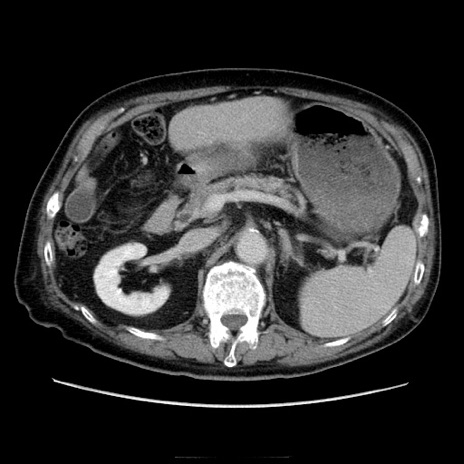

冠状断像

【症例】70歳代男性

【主訴】腹痛

【現病歴】肝硬変・肝細胞癌にてかかりつけの方。約9時間前に食後より腹痛出現。症状が徐々に増悪し、嘔吐出現したため来院。

【既往歴】肝硬変、肝細胞癌(RFA、TACE後)

【身体所見】意識清明、表情苦悶様、BT 36℃、BP 129/78mmHg、P 88bpm、SpO2 97%(RA)、右上腹部から心窩部にかけて圧痛あり、反跳痛なし、筋性防御あり。

【データ】WBC 5800、CRP 0.16